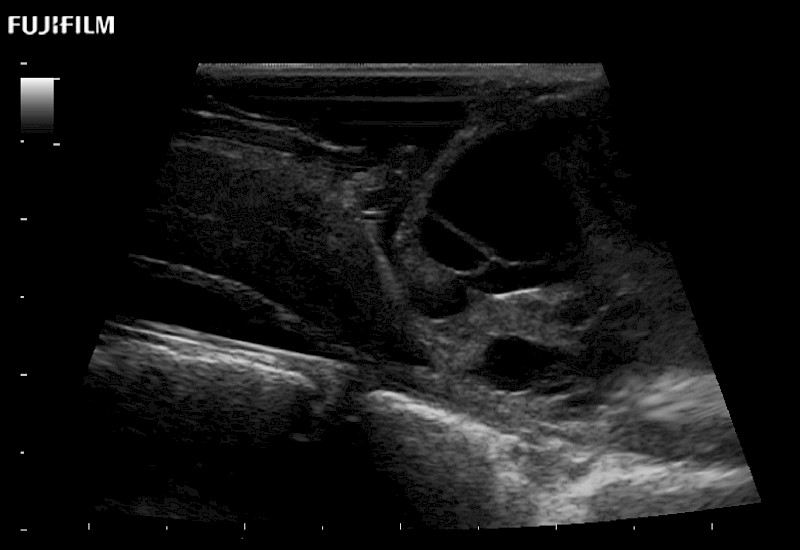

Exclusive 10mm side‐fire linear array transducer with 2.87mm diameter is ideal for real‐time visualization through and behind structures and instant, scalable definition of anatomy and vascularity including the ability to delineate and define tumor margins.

Hockey-stick linear array transducer is the transducer of choice for cervical spine scanning.